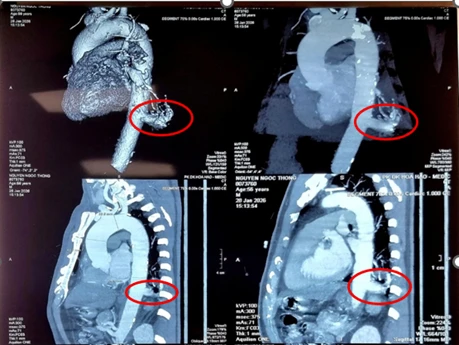

Người bệnh là ông N.N.T (56 tuổi, ngụ tỉnh Tây Ninh), tình cờ phát hiện tổn thương thùy dưới phổi trái khi khám sức khỏe tổng quát. Qua thăm khám và chẩn đoán, các bác sĩ xác định ông mắc phổi biệt lập nội thùy với khối kích thước 23 mm × 26 mm.

MSCT ngực cho thấy phổi biệt lập nội thùy trong thùy dưới phổi trái, có nhánh mạch máu nuôi lớn xuất phát từ động mạch chủ ngực.

Đáng chú ý, động mạch nuôi khối này xuất phát trực tiếp từ động mạch chủ ngực xuống có kích thước rất lớn với đường kính 17 mm, tiềm ẩn nguy cơ biến chứng nếu không được phát hiện và xử trí kịp thời.